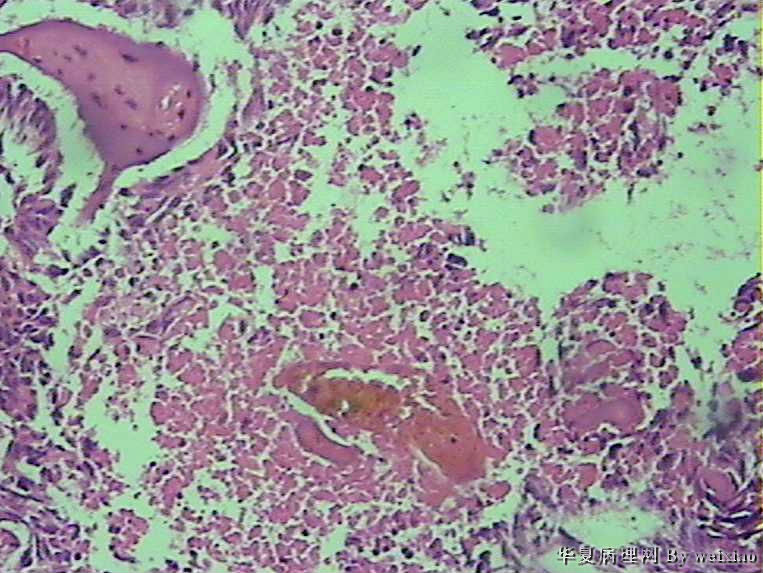

病史:男45岁,头痛2个月,手术所见:额叶占位性病变,与周围正常脑组  织的界限不清。

大体:灰白色碎组织一堆,质软,大小:2.5*1.8*1.3cm

胶质母细胞瘤

坏死+细胞密度+异性+围绕血管现象。

The tumor cells are kind of spindle, need to rule out gliosarcoma, you need to check MRI films, do immunostain for GFAP, and vimentin. The vascular proliferation (VP) supports GBM.

肿瘤细胞呈梭形,血管增生明显,有坏死,符合胶质母。